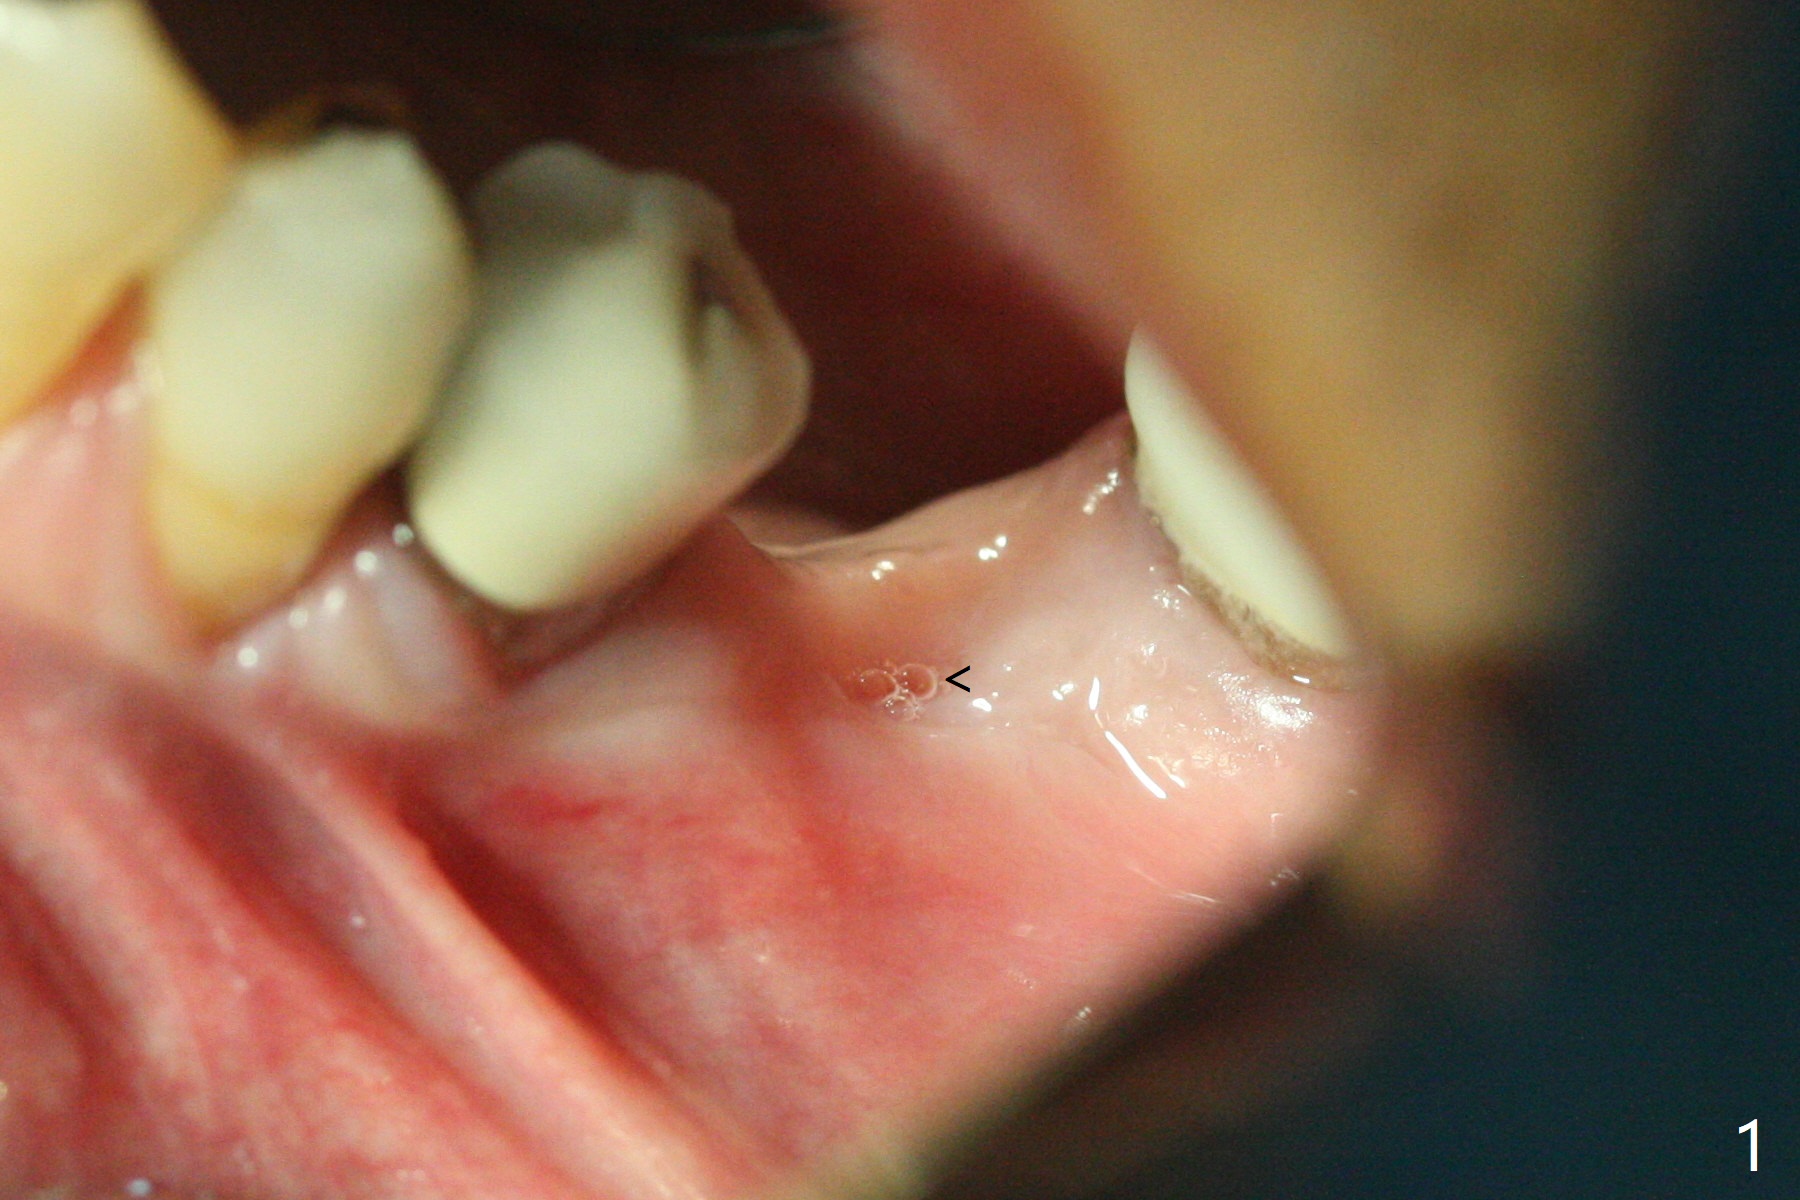

When the patient returns 4 months post implant removal and bone graft, the ridge at #19 is concave with a small hole which communicates with the underlying bone (Fig.1 <). The low density bone in the middle of the socket is ignored (Fig.2 *, 3 S (soft)). With under drilling, primary stability of tissue-level taps is lower. A bone-level dummy implant is placed with low torque (Fig.4). After removal of granulation tissue distal to the osteotomy, a larger implant is inserted with ~15 Ncm; mixture of autogenous bone and allograft is packed (Fig.5 *). The latter is covered by 12x12 mm BioXclude and sutured with 4/0 Chromic Gut tension free. 植牙后6.5月牙槽嵴饱满,角化龈宽(图六(刚开始浸润麻醉))。术后6.5月切开证实植体上面没有骨质覆盖(如图七:*),第一螺纹可能暴露(>)。由于骨质吸收,大号基台置入没阻挡,或者困难(图八),第一螺纹暴露(>)需要再次植骨(图九:*)。放置大号基台(6x6(4)毫米)和植骨使萎缩牙槽嵴部分得到修复(图十,与Uncover前(图六)对比)。Uncover时即刻置入修复性基台好处是利用基台牙龈外部分强化牙周敷料固定,基台中央放置一个棉球后,敷料可以插入基台中央进一步增加固位(图十一(舌侧观):*)。